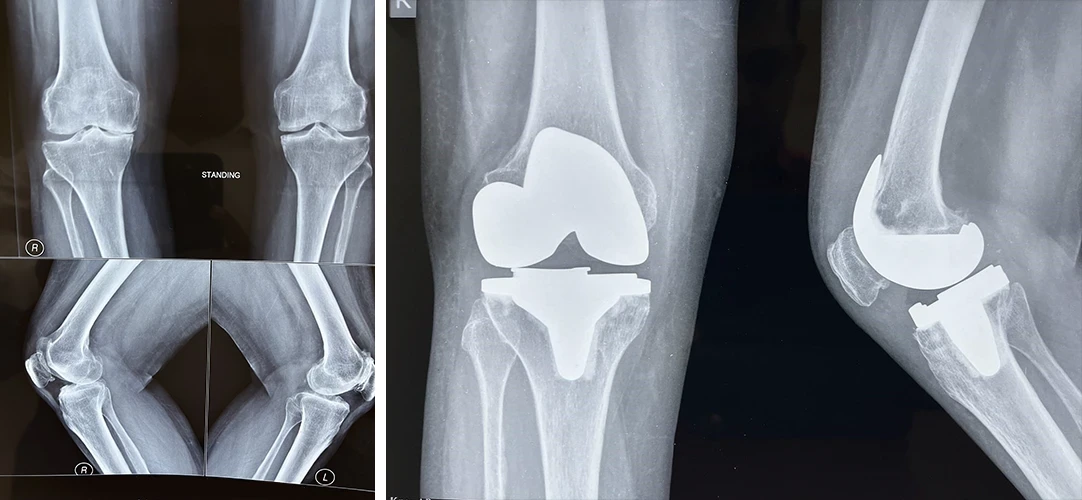

Total Knee Replacement

Are you having pain in your knees? Look no further, because Dr. Sanyal is the best choice for you. He specialises in total knee replacement surgery, offering you a solution to regain your mobility and live pain-free.